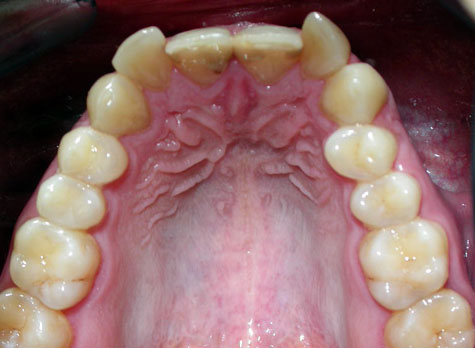

Пациент обратился с диагнозом индивидуальная макродентия.

Диагностика дополнительно выявила:- тенденцию к формированию мезиальной окклюзии,

- сужение и укорочение зубных рядов,

- ретрузию верхних центральных резцов,

- мезиальное смещение боковых отделов нижнего зубного ряда,

- ретрузию нижних резцов,

- множественные аномалии положения зубов.